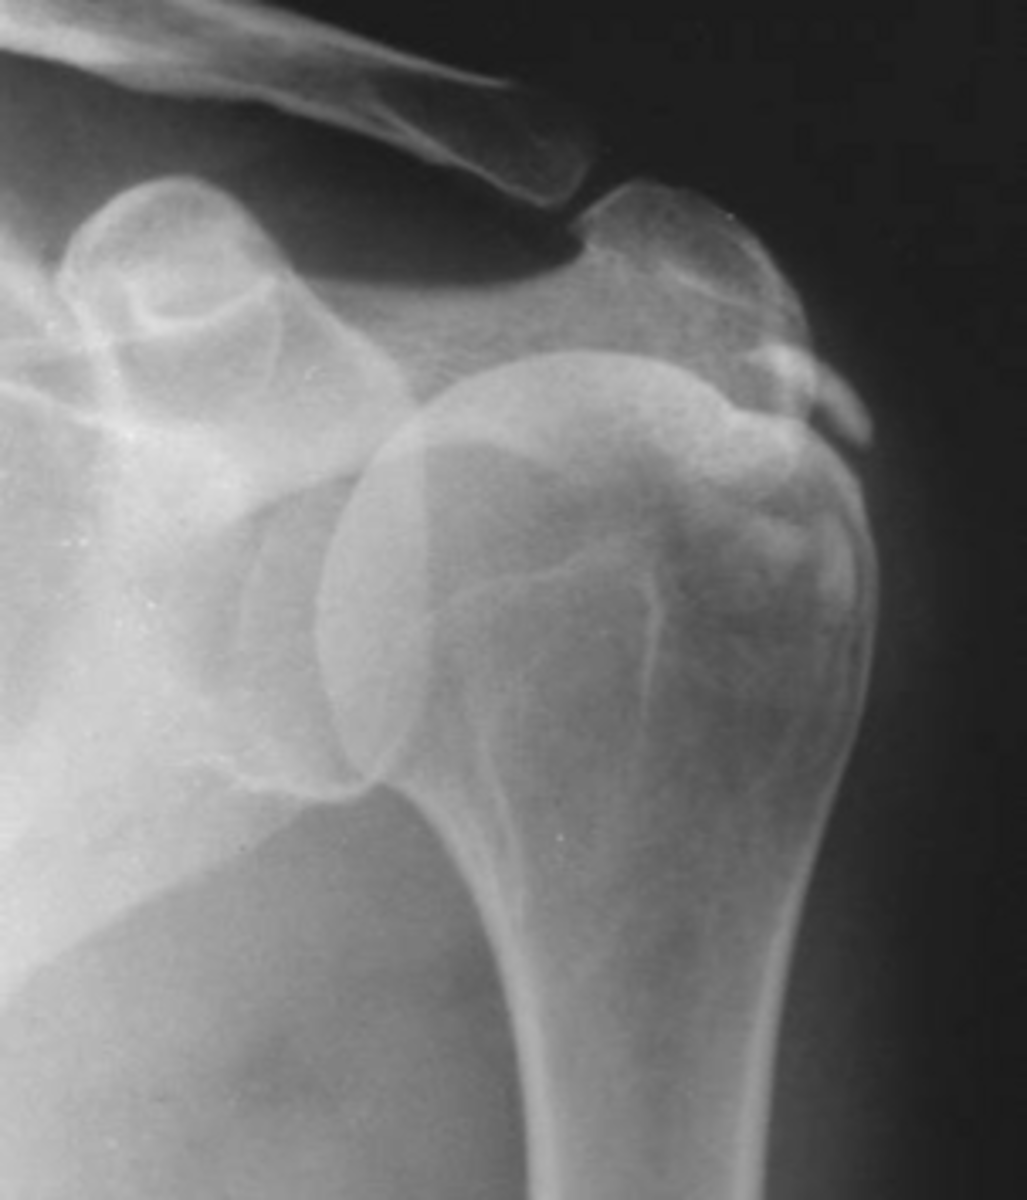

- Soft tissue swelling

- Chondrocalcinosis

- Severe degeneration

- Pyrophosphate arthropathy

- Articular destruction

State the radiographic findings of calcium pyrophosphate dihydrate crystal deposition disease (CCPD)